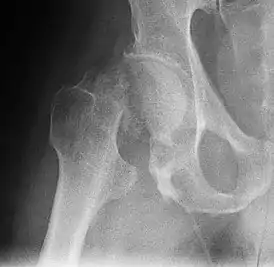

![]() Рентгенограмма, демонстрирующая перелом шейки бедра | |

4) Данных рентгенологического обследования — выполняется рентгенография тазобедренного сустава в прямой проекции. Наличие линии перелома на рентгенограмме служит окончательным, объективным подтверждением предварительно выставленного диагноза. Иногда для постановки диагноза может потребоваться магнитно-резонансная томография или компьютерная томография.